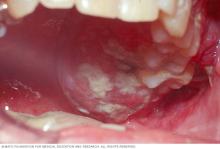

Mouth cancer — white patches

White patches in the mouth are one symptom of mouth cancer.

• A white or reddish patch on the inside of the mouth.

Leukoplakia

Leukoplakia appears as thick, white patches on the inside surfaces of the mouth. It has several possible causes, including repeated injury or irritation. It also can be a sign of mouth cancer or a sign of changes that could lead to cancer.

In a physical exam for mouth cancer, a healthcare professional looks at and feels your lips and mouth. That person checks for any lumps and areas of irritation. White patches in the mouth, called leukoplakia, and sores may be early signs of cancer.